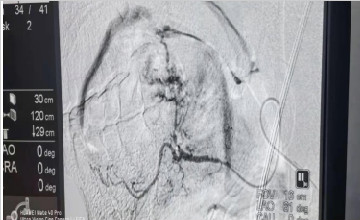

臨沂市第三人民醫(yī)院搶救一名舌根癌大出血患者

04-08

2021年4月5日下午,患者張大爺,舌根癌,之前已在山東省腫瘤醫(yī)院進(jìn)行了5周期化療,患者及家屬了解到我院擁有瓦里安調(diào)強放療設(shè)備及武霞主任豐富的放療經(jīng)驗,慕名而來。武主任...